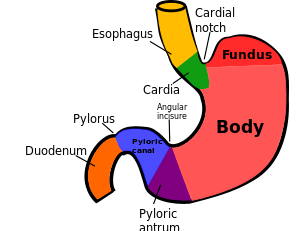

The stomach is a major organ of the gastrointestinal tract and digestive system. It is a consistently J-shaped organ joined to the esophagus at its upper end and to the duodenum at its lower end. Gastric acid (informally gastric juice), produced in the stomach plays a vital role in the digestive process, and mainly contains hydrochloric acid and sodium chloride. A peptide hormone, gastrin, produced by G cells in the gastric glands, stimulates the production of gastric juice which activates the digestive enzymes. Pepsinogen is a precursor enzyme (zymogen) produced by the gastric chief cells, and gastric acid activates this to the enzyme pepsin which begins the digestion of proteins. As these two chemicals would damage the stomach wall, mucus is secreted by innumerable gastric glands in the stomach, to provide a slimy protective layer against the damaging effects of the chemicals.

At the same time that protein is being digested, mechanical churning occurs through the action of peristalsis, waves of muscular contractions that move along the stomach wall. This allows the mass of food to further mix with the digestive enzymes. Gastric lipase secreted by the chief cells in the fundic glands in the gastric mucosa of the stomach, is an acidic lipase, in contrast with the alkaline pancreatic lipase. This breaks down fats to some degree though is not as efficient as the pancreatic lipase.

The pylorus, the lowest section of the stomach which attaches to the duodenum via the pyloric canal, contains countless glands which secrete digestive enzymes including gastrin. After an hour or two, a thick semi-liquid called chyme is produced. When the pyloric sphincter, or valve opens, chyme enters the duodenum where it mixes further with digestive enzymes from the pancreas, and then passes through the small intestine, where digestion continues. When the chyme is fully digested, it is absorbed into the blood. 95% of absorption of nutrients occurs in the small intestine. Water and minerals are reabsorbed back into the blood in the colon of the large intestine, where the environment is slightly acidic. Some vitamins, such as biotin and vitamin K produced by bacteria in the gut flora of the colon are also absorbed.

The parietal cells in the fundus of the stomach, produce a glycoprotein called intrinsic factor which is essential for the absorption of vitamin B12. Vitamin B12 (cobalamin), is carried to, and through the stomach, bound to a glycoprotein secreted by the salivary glands - transcobalamin I also called haptocorrin, which protects the acid-sensitive vitamin from the acidic stomach contents. Once in the more neutral duodenum, pancreatic enzymes break down the protective glycoprotein. The freed vitamin B12 then binds to intrinsic factor which is then absorbed by the enterocytes in the ileum.

The stomach is a distensible organ and can normally expand to hold about one litre of food.[22] This expansion is enabled by a series of gastric folds in the inner walls of the stomach. The stomach of a newborn baby will only be able to expand to retain about 30 ml.